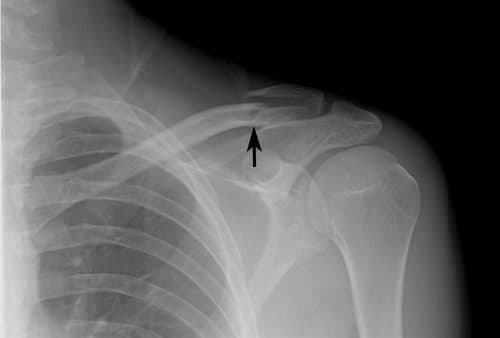

Nếu có nghi ngờ rằng xương đòn của bạn bị gãy, các bác sĩ sẽ khuyên bạn nên chụp X-quang vai để chẩn đoán thêm. X-quang có thể hiển thị hình ảnh của xương đòn bị gãy và mức độ nghiêm trọng của nó hoặc xương khác có bị gãy hay không. Trong một số trường hợp, nếu các bác sĩ cần phải xem xét các vết nứt một cách chi tiết hơn, họ sẽ áp dụng chụp cắt lớp vi tính (CT scan).